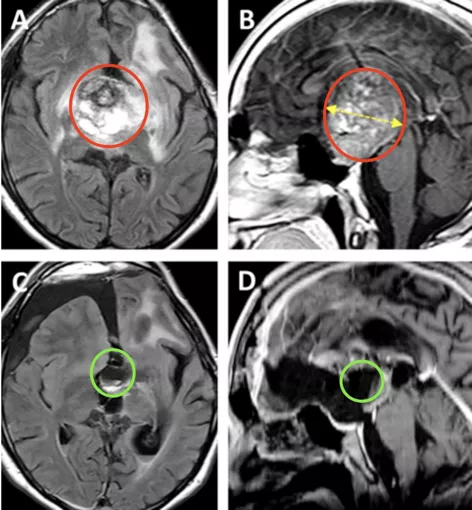

16岁的Nico是个阳光开朗的大男孩,但可能很少有人知道,他还是一个与脑瘤抗争了10年之久、深受其害的年轻患者。早在他4岁的时候,他就因丘脑肿瘤而做过左侧翼点入路切除手术,但手术并不完全。在确诊为“丘脑毛细胞星形细胞瘤”后,他还做了两个周期的辅助化疗,但仿佛都无济于事。肿瘤在随后的10年多里中很快复发长大,Nico也出现了全垂体功能减退和严重的左侧视力障碍,几乎等于这只眼睛失明。

二次手术的Nico已经承担不了这诸多的手术风险,他脑子里的较大肿瘤到底能不能顺利切除?Nico的垂体功能还能恢复吗?他还能回归本来的生活和学习吗?种种这些疑问,没想到在Nico16岁的时候终于找到了答案。来自INC国际神经外科医生集团、现任国际神经外科联合会WFNS教育委员会主席、德国INI国际神经学研究所神经外科教授Helmut Bertalanffy(巴特朗菲)为Nico进行了脑瘤手术,近乎全切,也正是这场手术决定着Nico术后的良好恢复、更长的生存期和更佳的生活质量。

图A、B为术前MRI影像。图C、D显示为几乎全切的术后MRI